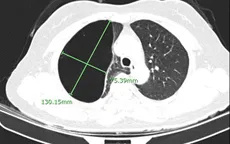

VTV.vn - Sau thời gian dài bị đau tức ngực, người bệnh N.T.H., sinh năm 1966 đã được các bác sĩ Bệnh viện đa khoa tỉnh Phú Thọ cắt khối kén khí phổi kích thước khoảng 13x7cm.